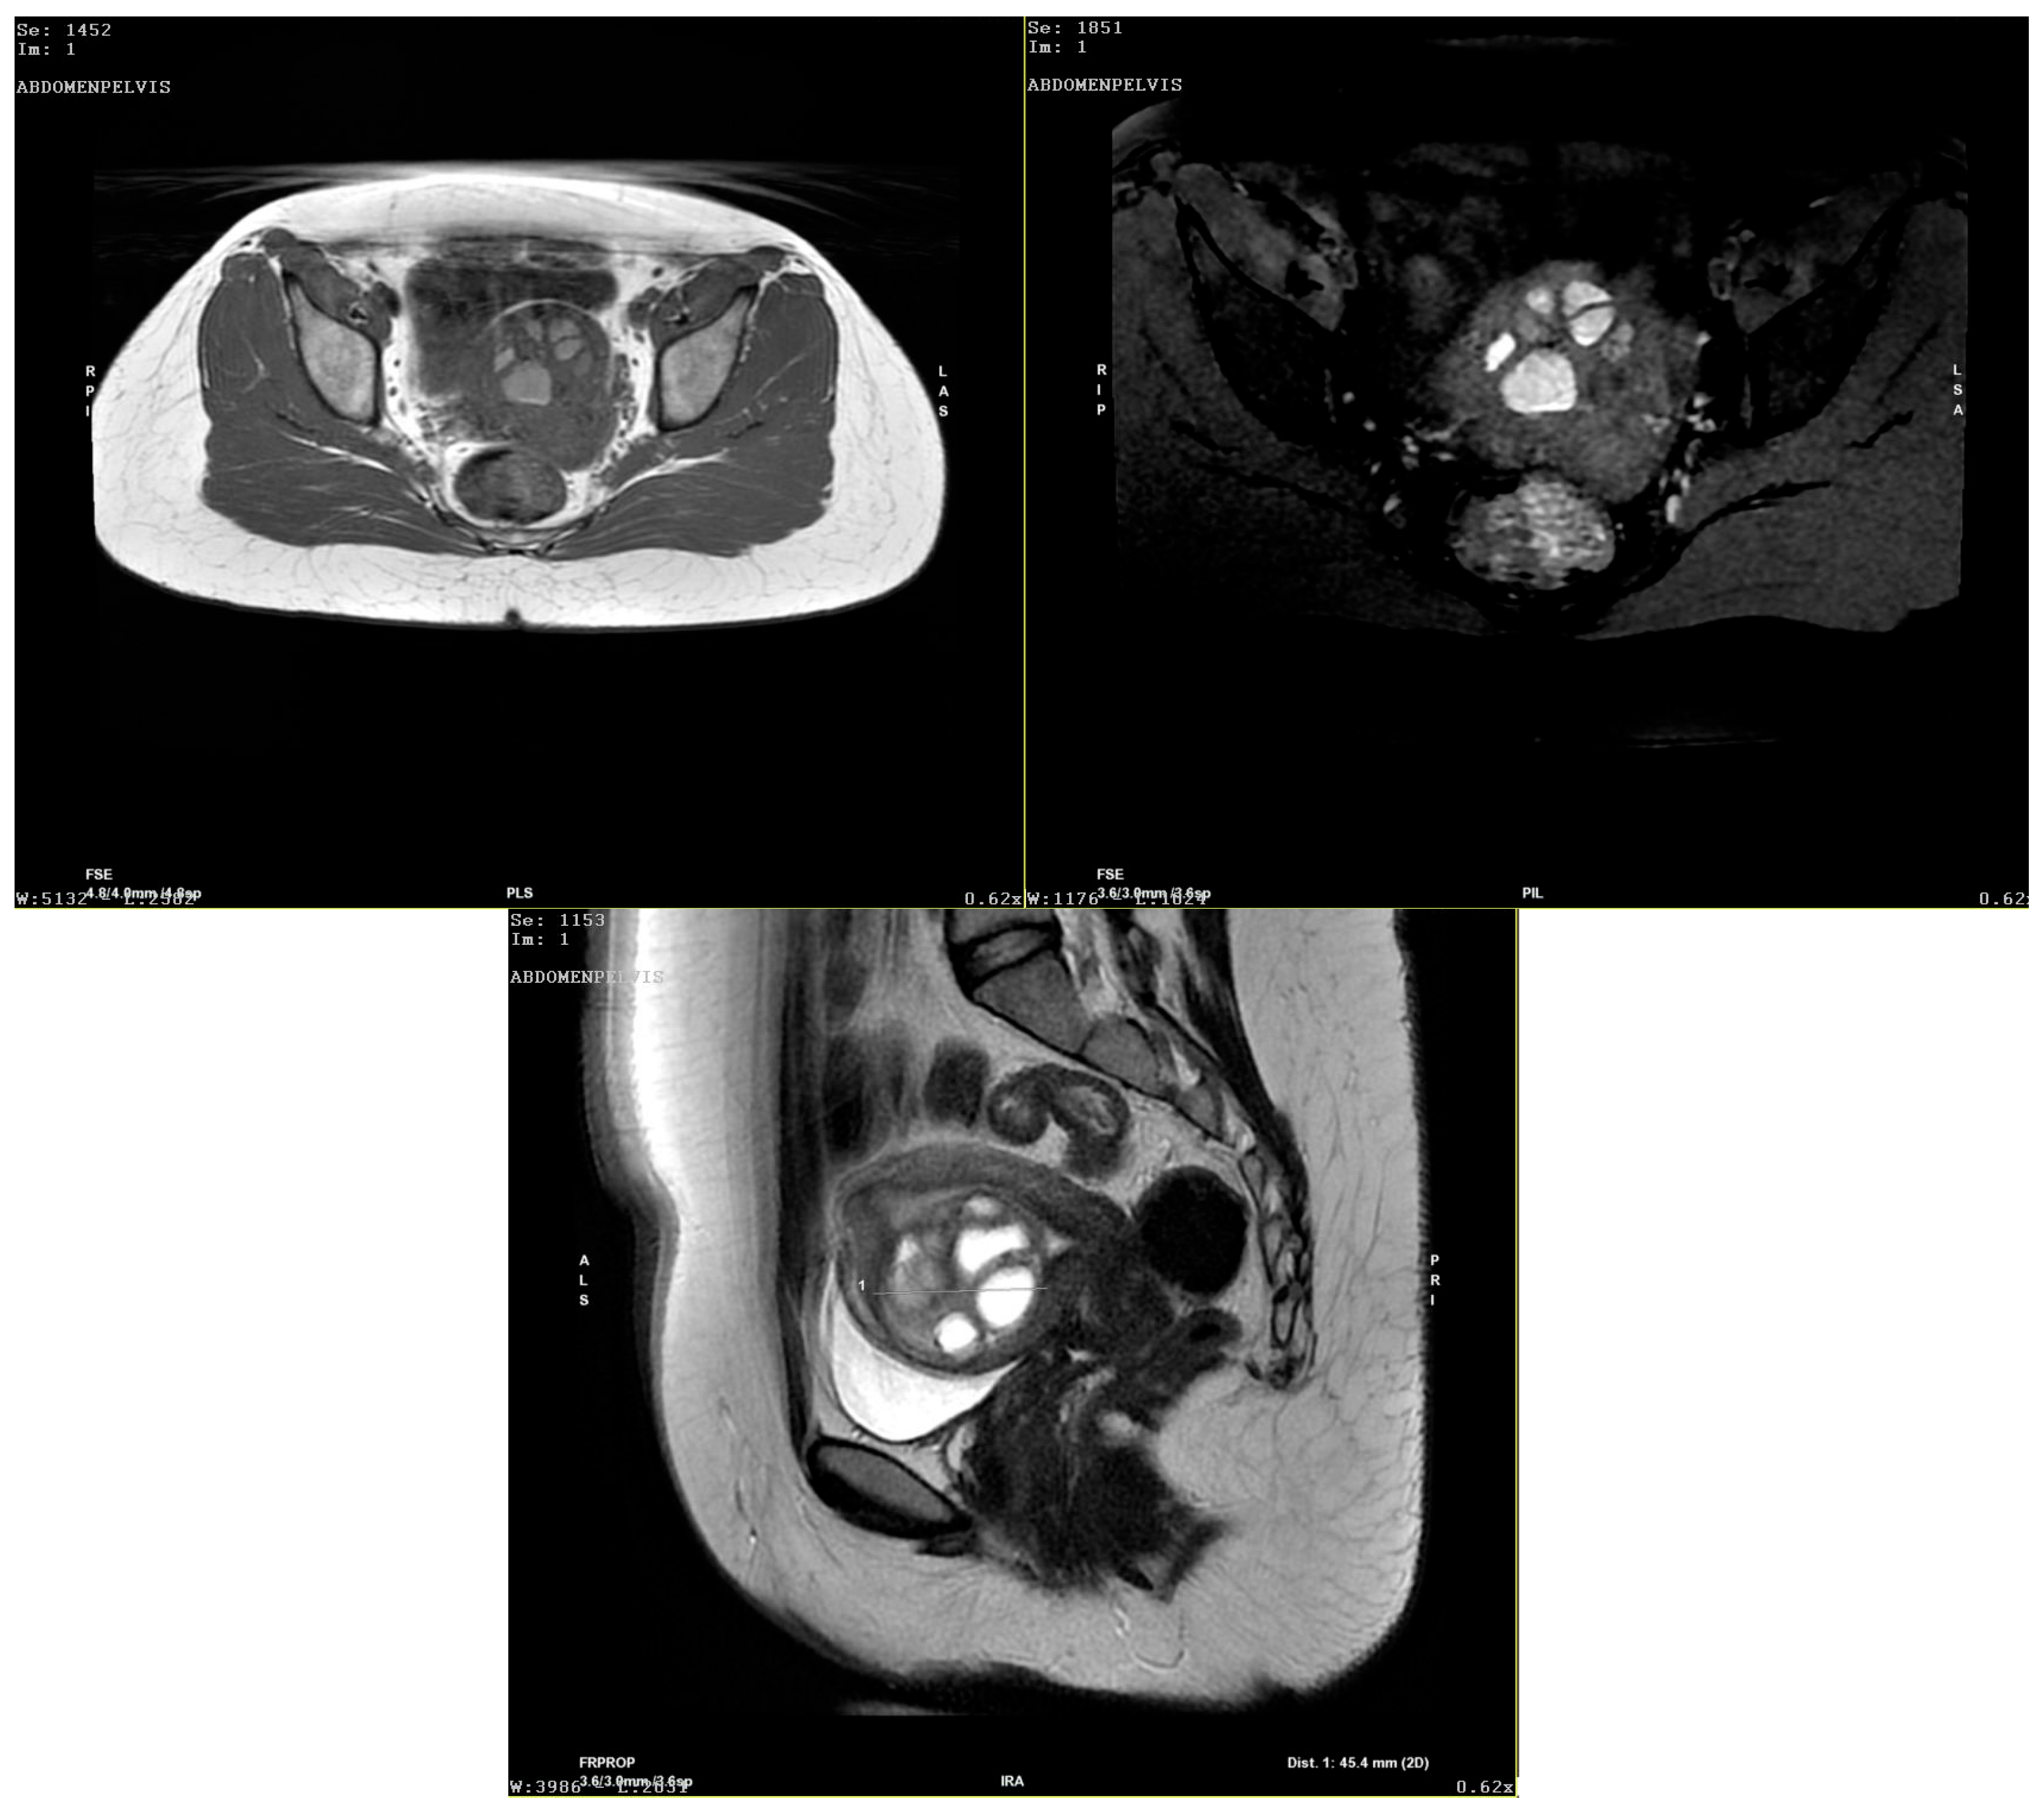

STUMP Swiftly Followed by Large Adenomyoma in a Young Nulliparous Patient

Nemeti, G.; Cruciat, G.; Goidescu, I.G.; Roberta, C.; Ticala, V.M.; Surcel, M.; Goidescu, C.M.; Staicu, A.; Boitor-Borza, D.; Fetica, B.; et al. STUMP Swiftly Followed by Large Adenomyoma in a Young Nulliparous Patient. Diagnostics 2025, 15, 3018. https://doi.org/10.3390/diagnostics15233018